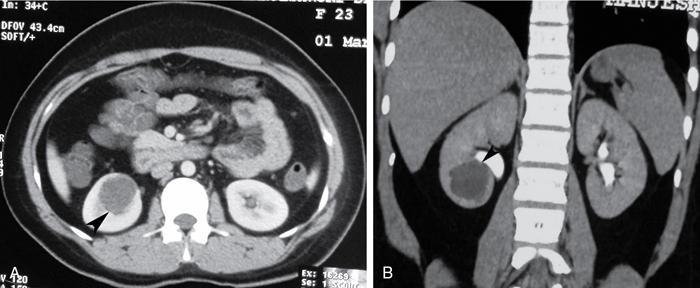

Simple renal cysts are usually asymptomatic, and incidentally detected, unless complicated. Complications include haemorrhage, infection, rupture, and caliceal or renal pelvic obstruction (Fig. 10.12.1.1).

- Imaging: Uncomplicated simple cysts are Bosniak type 1 cyst, characterized by thin hairline wall, and no septation, calcification or enhancement that are of water density (0–20 HU) on CT, and anechoic on USG.